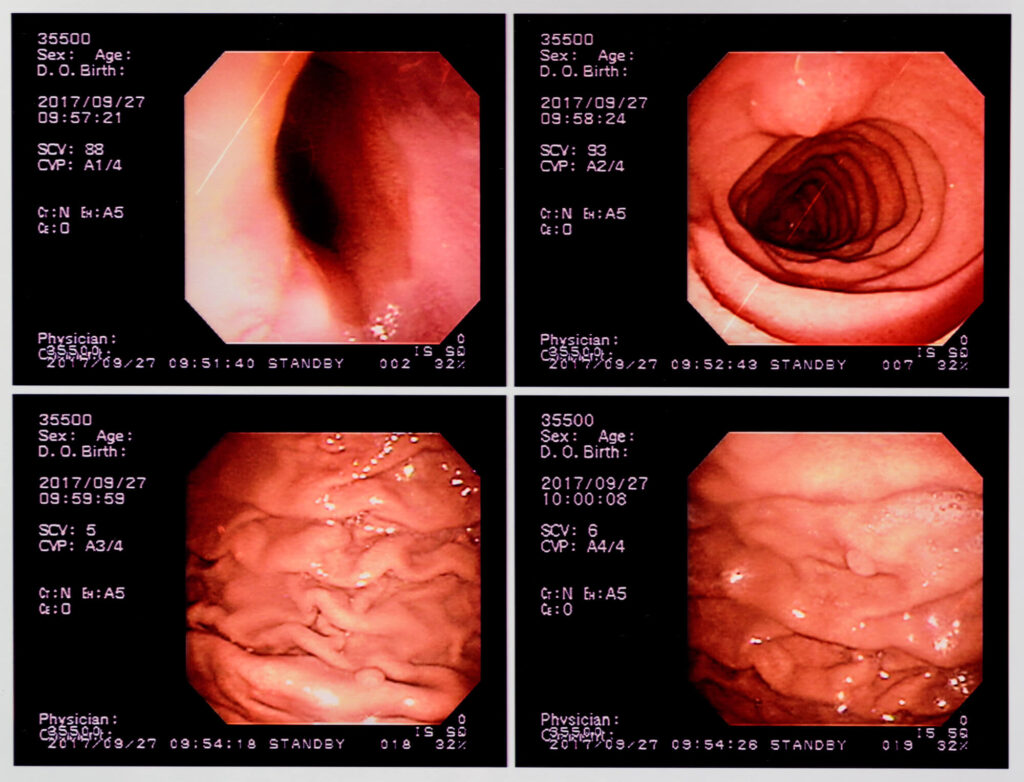

一方、胃カメラは口や鼻から内視鏡を挿入し、食道から胃、十二指腸の粘膜を直接観察できます。粘膜の色調や小さな凹凸の変化も確認できるため、早期の胃がんや微細な異常の発見にも適しています。